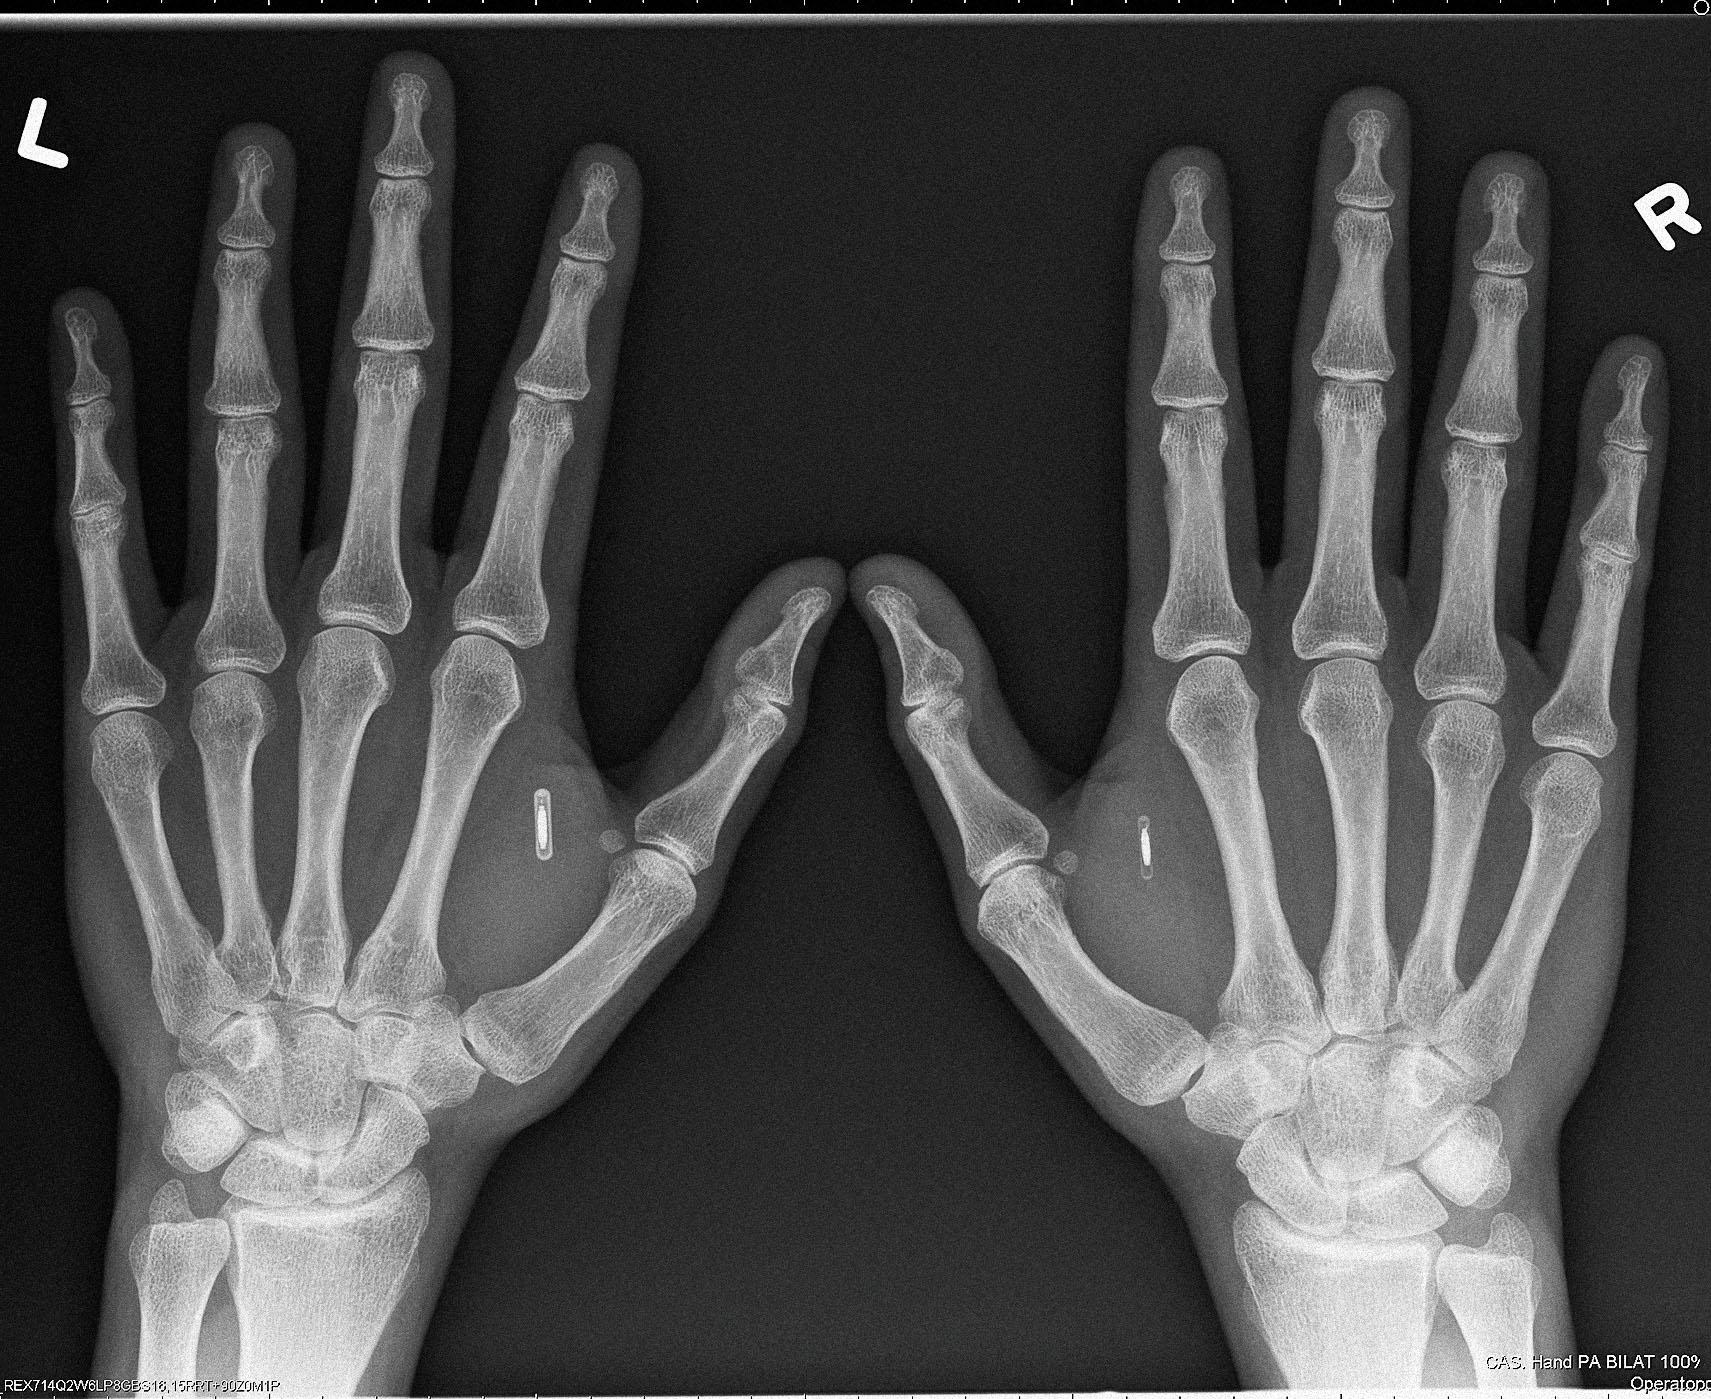

Цена на чипы разнится в зависимости от серии. Серия X — самые популярные из-за простоты установки NFC- и RFID-транспондеры. Их Dangerous Things продает по $79, они не требуют подзарядки и способны нести информацию о пользователе, его электронные ключи. Следующая серия — Flex. Это чип в гибком биополимере стоимостью $200. Если девайсы серии X можно вживить только под кожу между большим и указательным пальцем «ветеринарной» иглой с чуть увеличенным диаметром, то Flex размещаются чуть выше запястья, а их «установка» требует небольшой хирургической операции.

Срок годности чипов, по словам Граафстры, до 30 лет. В интернет-магазине Dangerous Things продаются также необходимые для проведения операции (иглы, скальпели, обезболивающие и т.д.) и программирования микрочипов инструменты (ридеры, стикеры и т. д.). Граафстра постоянно разрабатывает новые устройства, с которыми взаимодействуют импланты, например «умное» ружье, стреляющее только в руках владельца. В последнее время предприниматель работает над проектом VivoKey. Это вживленное в руку зашифрованное хранилище данных. «Главная цель устройства — переместить ключи шифрования данных туда, где их не смогут достать злоумышленники», — рассказывает Амаль.